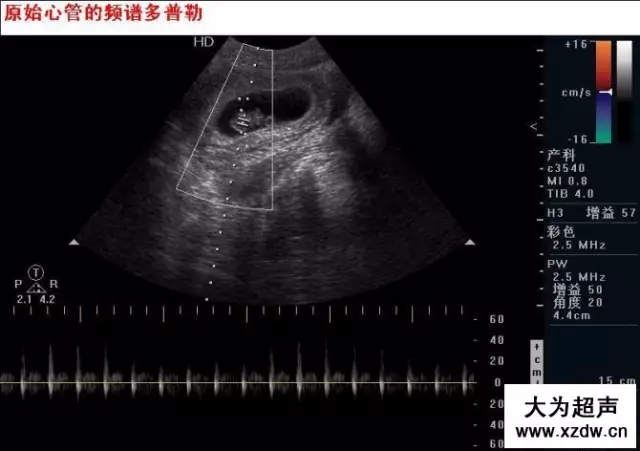

產科超聲正常圖片